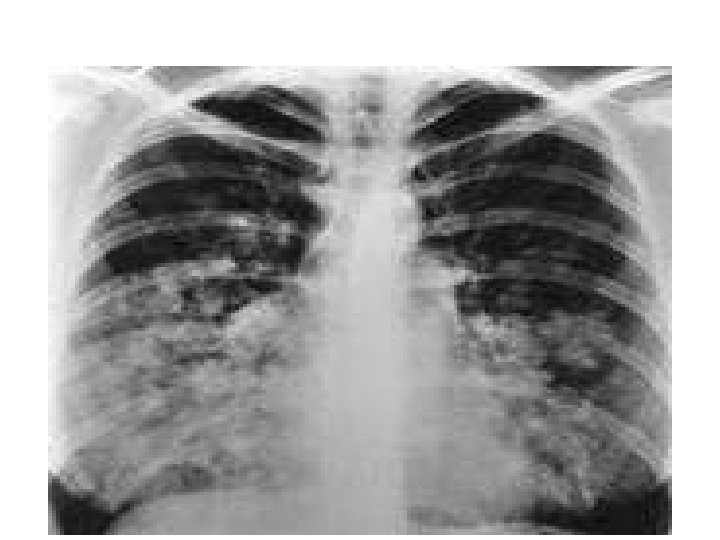

HAPE Above 4500 m (14, 760 ft) Pathophysiology • Severe pulmonary Hypertension • Some areas pulmonary vascular bed overperfused • Blood vessel injury • Fluid leak into lung • Lung edema – water – Worsens gas exchange Clinical • 2 – 4 days after arrival • SOB • Cough • Hemoptysis • Dx – Crackles – Xray

HAPE Treatment • • • Oxygen Descent Hyperbaric chamber Positive Pressure Ventilation B – agonist inhalers Pulmonary vasodilators – Nifedipine – sildenafil